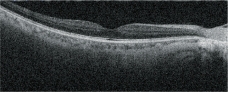

OCT靈敏度可選

根據病歷,通過選擇適宜的OCT靈敏度,以確保對介質渾濁患者的圖像采集。